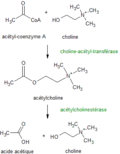

Neurotransmitter synthesized in neurons are divided into two major categories: small-molecule neurotransmitter and neuropeptide. Small-molecule neurotransmitters are synthesized within the axon terminal(e.g.acetylcholine (ACh)). Some of the precursors for the synthesis of these molecules are taken up by selective transporters on the membrane of the terminal. Others are byproducts of cellular processes within the neuron and are thus readily available. Neuropeptide are different from small-molecule neurotransmitters in both size and in the way of the synthesis. Neuropeptides generally range from 3 to 36 amino acids in length. So, they are larger than small-molecule neurotransmitters. Small neurotansmitters are made within the axon terminal as they need the simple enzymatic reactions but neuropeptides are made in the cell body as their synthesis requires peptide bond formation.The synthesis of a neuropeptide is similar to the process of any secretory protein within the cell. First, within the cell nucleus, during which a specific peptide-coding sequence of DNA,gene transcription takes place and It is used as a template to build a corresponding strand of messenger RNA. The mRNA then travels to a ribosome, where the process of translation begins. During translation, the sequence of the mRNA act as a code to string together a corresponding sequence of amino acids that will become the neuropeptide needed at the terminal. Before this molecule can be transported to the terminal for release into the synaptic cleft, it must be processed in the endoplasmic reticulum (ER), packaged in the golgi apparatus, and transported in storage vesicles down the axon to the terminal.

Acetylcholine metabolisme

Acetylcholine metabolisme -